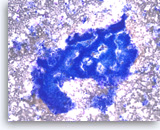

Intraductal papillary mucinous neoplasm #3,

Pancreas FNA, Cell Block.

The tumor cells have high nuclear to cytoplasmic ratio and hyperchromatic nuclei and form papillary architectures. The cigar-shaped nuclei are indicative of the “intestinal type” of IPMN, according to the WHO classification, and there is focal true stratification indicative of high grade dysplasia.

20X

Intraductal papillary mucinous neoplasm #3,

Pancreas FNA, Cell Block.

The tumor cells have high nuclear to cytoplasmic ratio and hyperchromatic nuclei and form papillary architectures. The cigar-shaped nuclei are indicative of the “intestinal type” of IPMN, according to the WHO classification, and there is focal true stratification indicative of high grade dysplasia.

20X